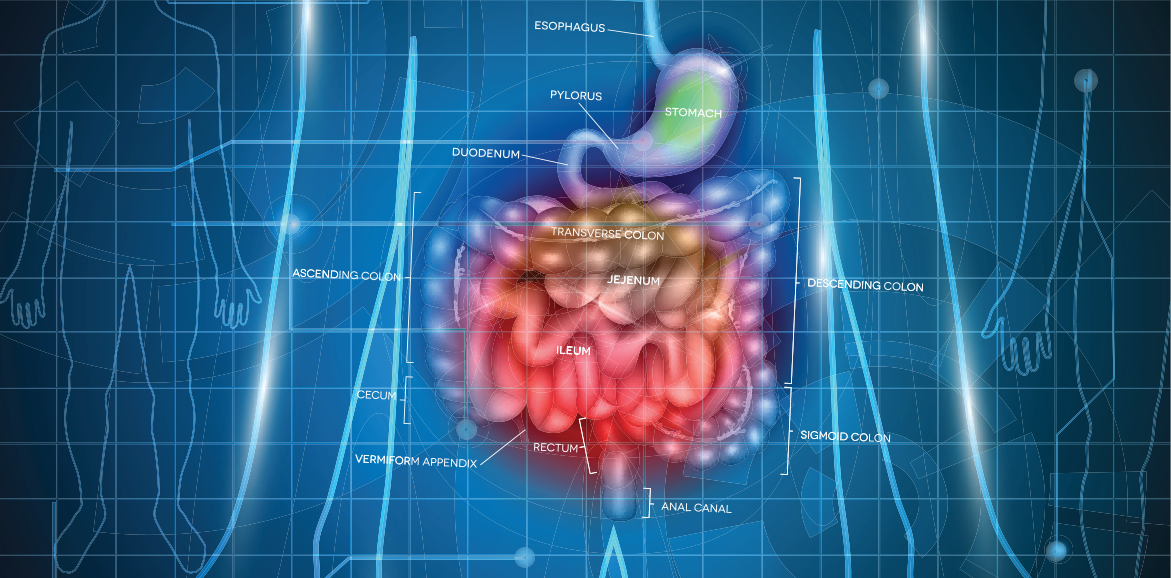

혹시 오리직장이라는 말씀을 들어보신 적이 있으십니까? 오리의 창자는 일직선으로 되어 있어서 변을 잘 보기 때문에 무슨 일이든지 소화를 잘 시키는 사람을 오리직장이라고 합니다. 이처럼 음식을 먹은 후에 바로 소화를 잘시키고 배설이 잘 되면 좋겠지만 그렇지 못한 사람들은 변비가 생겨 괴롭다고 합니다.

변비가 오래되면 식욕이 저하되고 소화도 잘 안되고, 속이 미식거리는 증상이 나타납니다. 심한 경우에는 구토를 하기도 합니다. 그 밖에 장내에 대변이 항상 남아 있어서 흔히 말하는 똥배의 원인이 되기도 하고 각종 질환의 원인이 되기도 합니다.

또한, 갑상선 기능저하증, 당뇨병, 파킨슨병, 다발성경화증, 하반신마비 등의 전신적 질환이 있는 사람들의 경우, 대부분 변비가 있습니다. 집안에 음식물 찌꺼기가 조금만 썩어도 온 집안에 냄새로 견딜수 없는데, 몸안에서 이러한 현상이 있다면 어떻하겠습니까? 반드시 치료해야겠지요. 여기서 성경말씀을 잠시 살펴본 후에 그 치료 방법을 말씀드리겠습니다.

자 그럼 어떻게 하는 것이 변비 예방과 치료에 좋은지를 알아보겠습니다. 많은 사람들이 변비 예방법으로 섬유질이 많은 식사법등을 통해 장의 운동을 활발하게 하는 것들을 권하지만, 이 방법은 약간의 도움은 줄 수 있어도 예방과 치료법은 못됩니다. 변비에 걸렸다는 것은 피를 만들어주는 장기가 활동을 하지 않는다는 것이므로 굉장히 심각한 상황입니다.